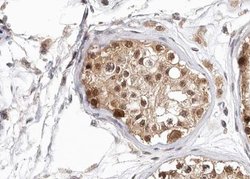

| Immunohistochemistry (Paraffin), Western Blot, Immunocytochemistry | |